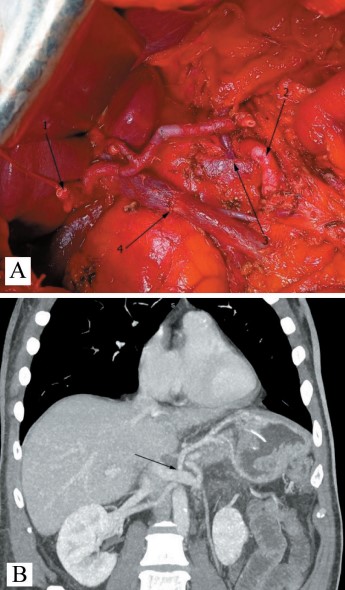

2. Рис. 2. A. TП с ПВР: 1 – культя общего желчного протока; 2 – верхняя брыжеечная артерия; 3 – анастомоз левой желудочной и левой почечной вен; 4 – портомезентериальный анастомоз. Б. КТ скан того же пациента на 7-е сут после операции. Стрелка указывает на хорошо функционирующий венозный анастомоз. Примечание: рисунок выполнен авторами | |